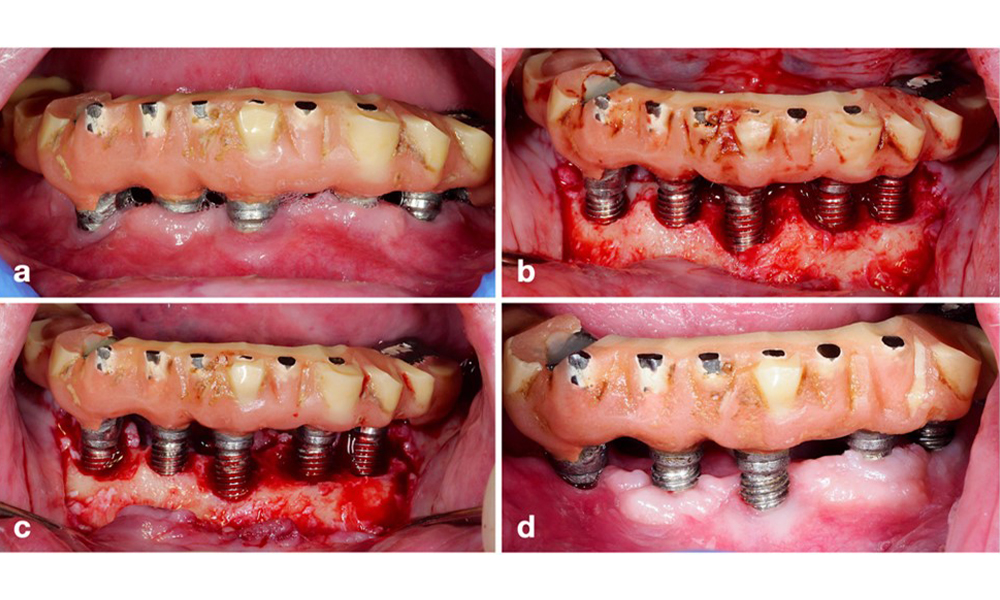

Протетичната реставрация трябва да бъде отстранена както по време на нехирургично, така и по време на хирургично лечение, за да се подобри достъпът до повърхността на импланта. Изборът на хирургична интервенция (напр. резективна, реконструктивна или комбинирана) зависи от няколко фактора: (1) морфология на дефекта (напр. хоризонтална, дехисценция, вътрекостна или комбинирана) (фигура 10), (2) повърхност на импланта ( т.е. обърната или модифицирана/"груба") и (3) наличие или липса на достатъчно кератинизирана и прикрепена лигавица.